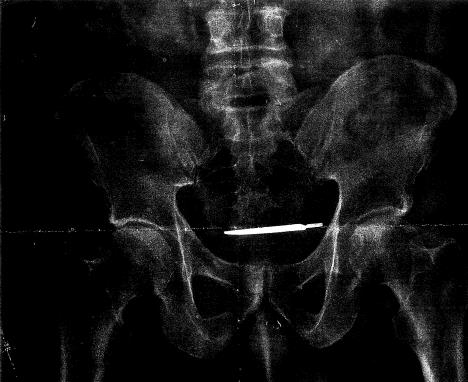

Nakon dugogodišnjih bolova u stomaku, američki vojni veteran otkrio je da mu je u stomaku ostao skalpel tokom operacije koju je imao u vojnoj bolnici u Konektiketu.

Kada mu je urađen rengenski snimak, lekari su imali šta i da vide. Naravno, Tarner je odmah upućen na još jednu operaciju nakon koje su lekari potvrdili da je reč o istom skalpelu kojim je operisan pre četiri godine.